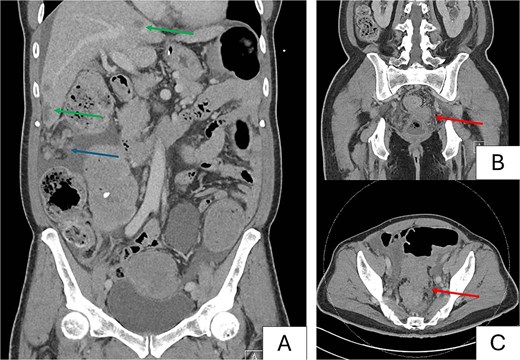

A contrasted computed tomography (CT) scan of the thorax, abdomen and pelvis demonstrated an obstructing 8.6 × 5.3 cm rectosigmoid colonic mass with 2.4 × 2.1 cm extraserosal extension. Extensive peritoneal nodules measuring up to 6.1 × 3.4 cm, multiple hypo-enhancing bilobar hepatic nodules up to 2.4 cm (Fig. 2A) and bilateral pulmonary nodules measuring up to 0.7 cm were reported as suspicious for metastases. He had a hemoglobin count of 9.4 g/dL, alkaline phosphatase of 208 U/L and carcinoembryonic antigen (CEA) of 140 ug/L.

Preoperative computed tomography images. Images demonstrate a metastatic rectosigmoid mass with suspicious nodules in liver and peritoneum with features of large bowel obstruction. (A) Coronal image demonstrating bulky peritoneal nodules (blue arrow), and bilobar hepatic nodules suspicious for metastases (green arrows). (B) Coronal image demonstrating primary rectosigmoid tumor (red arrow). (C) Axial image demonstrating tumor with pericolonic nodules suspicious for nodal involvement (red arrow).